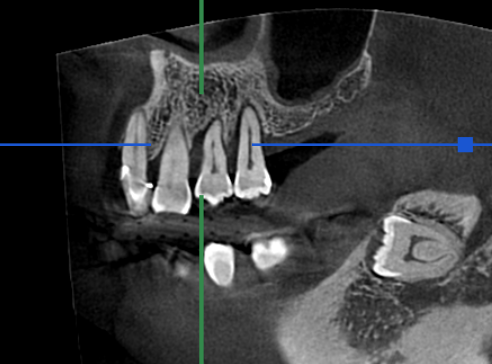

| 備考 | CT画像より右上4番の近心歯周ポケットが根尖近くまで存在し、口蓋側まで繋がっており、予後不良と判断してインプラント治療を行う予定とした。 右上5番は口蓋側に根尖付近のポケットがあったが咬合性外傷による動揺であり、保存可能と判断。 4番骨造成時にフラップ手術を行った。 |